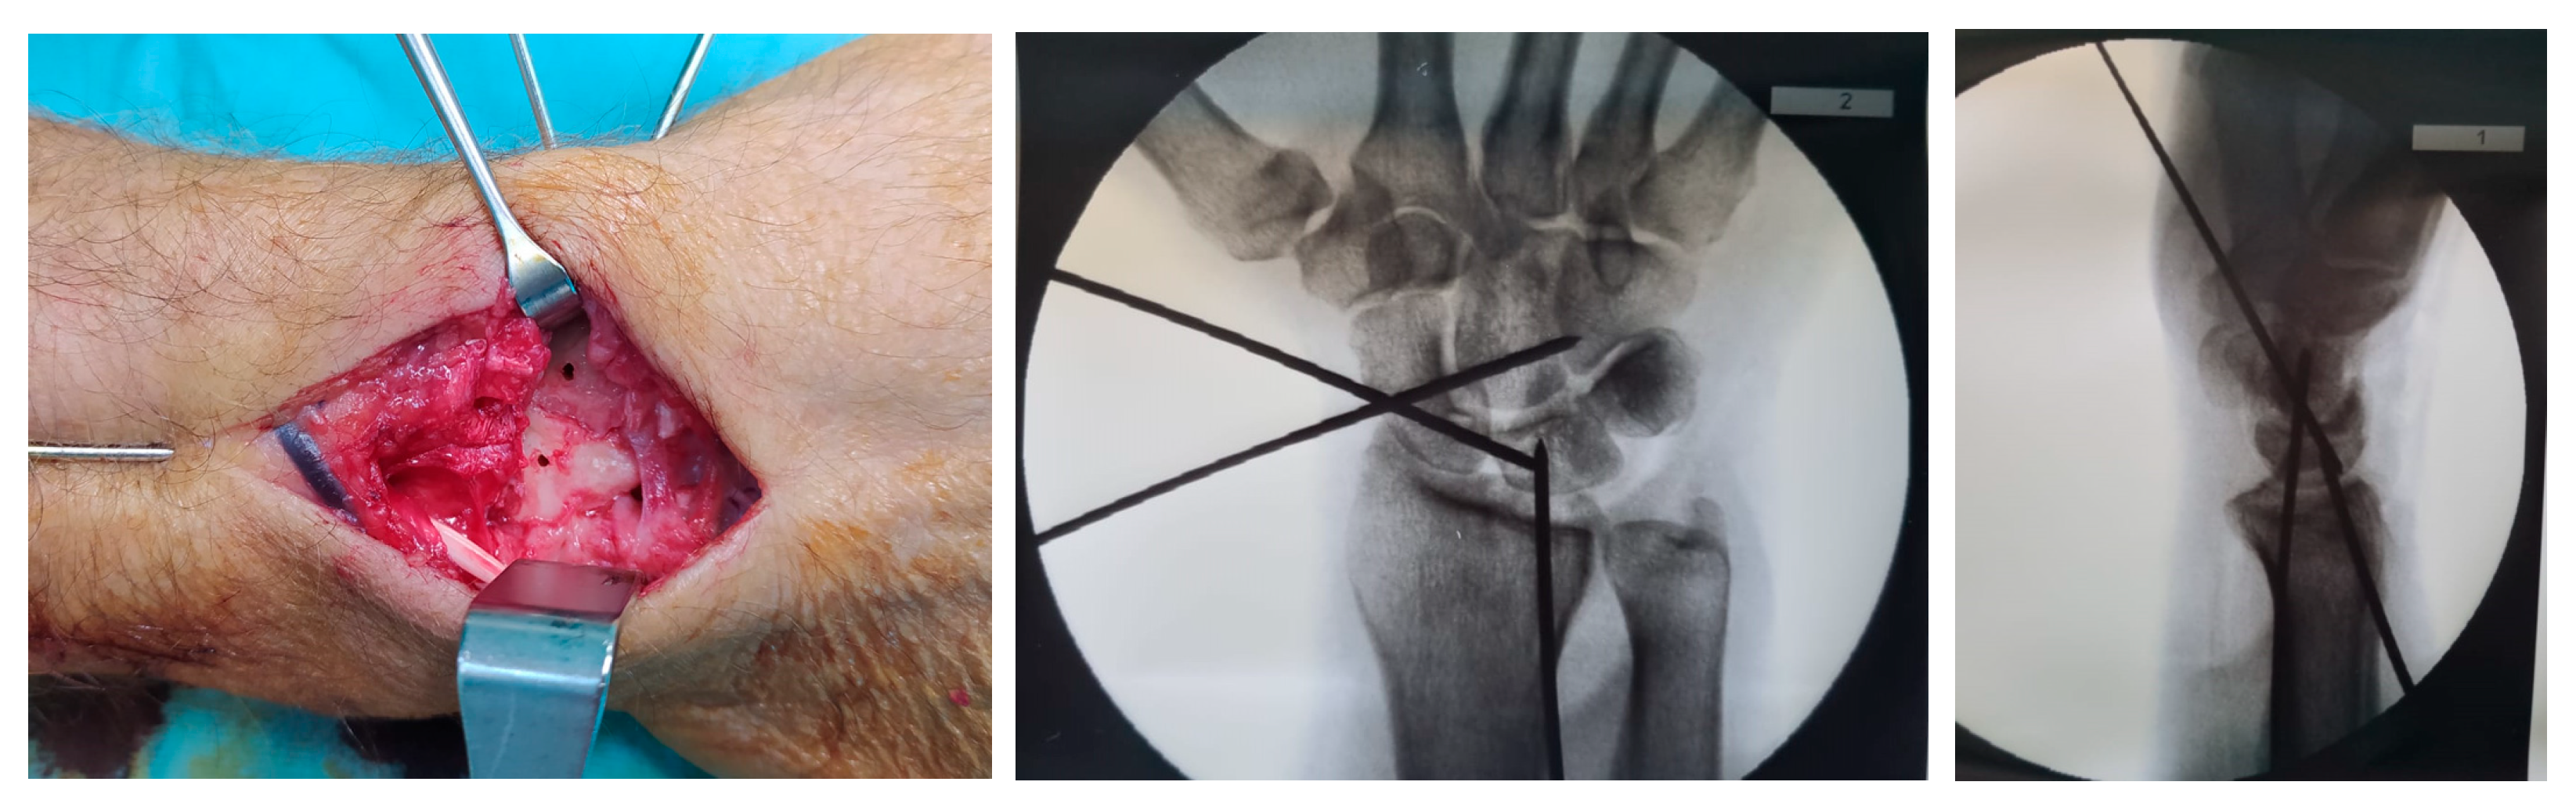

2.3. Surgical Technique

2.3.2. Surgical Procedure